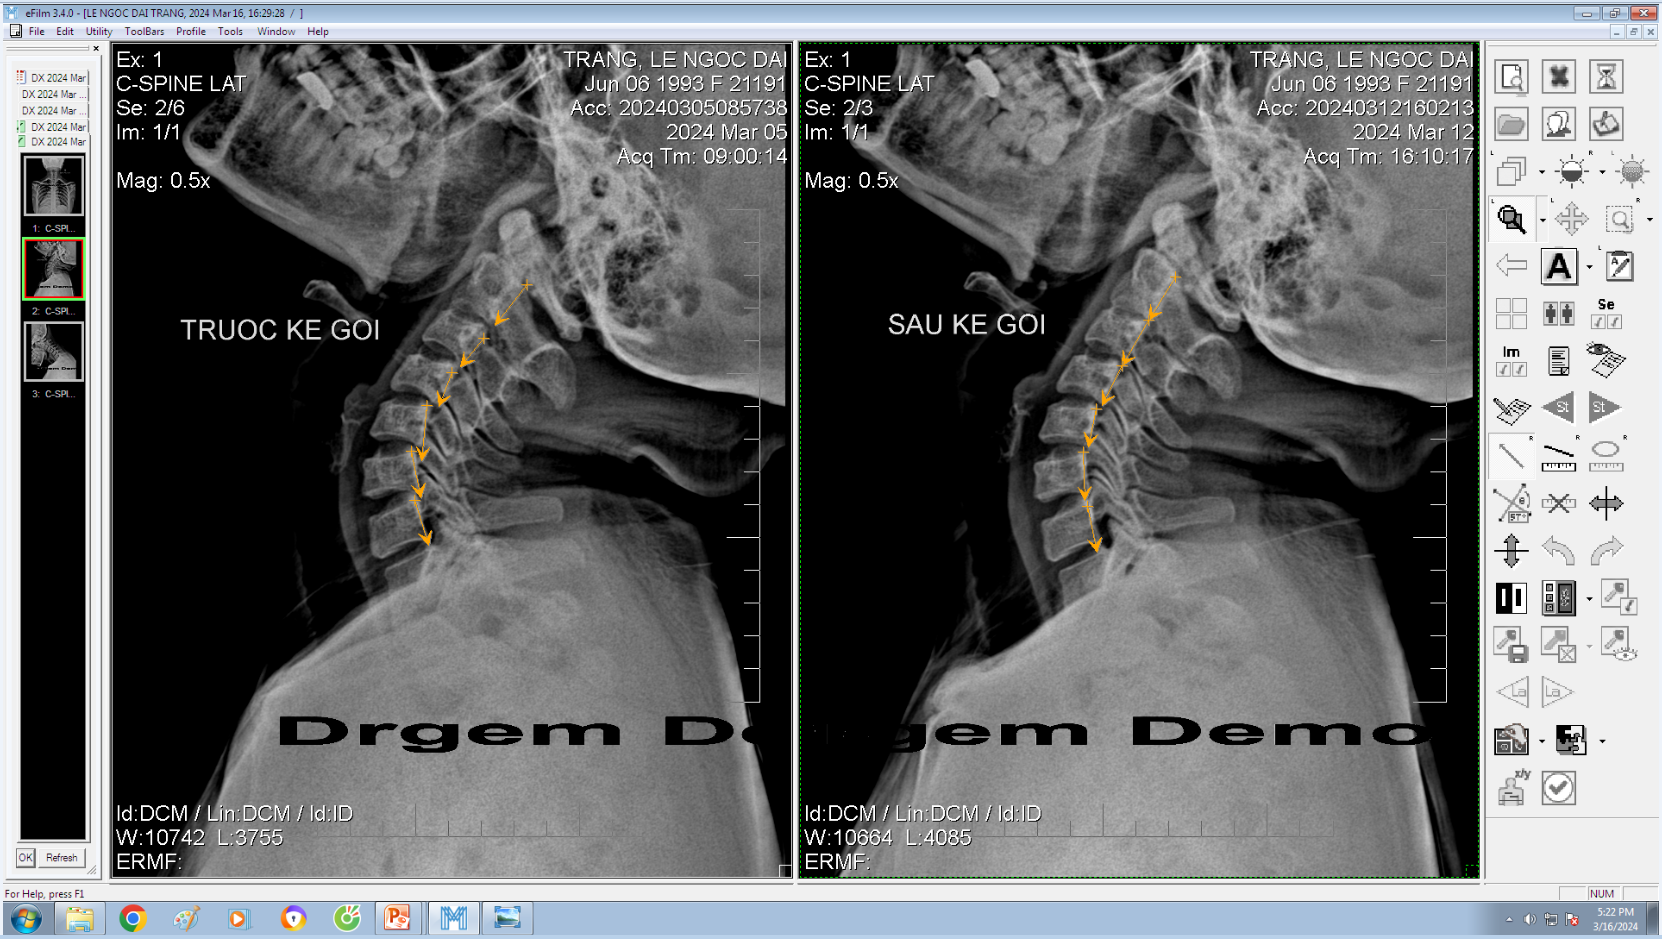

DOCTORLOAN đã thành công trong điều chỉnh xương khớp về đúng vị trí trong thời gian ngắn